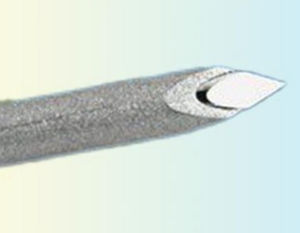

... 带有套管针尖的活检针可轻松插入,针尖的特殊形状可带来最佳的组织取材效果。使用特殊的提取针和活检针的锥形内腔相结合,可牢牢固定组织样本。推针上的标记可显示针内是否含有足够的样本组织。在不使用抽取针的情况下使用推杆时,可提供插入辅助工具。 包括1 个鲁尔帽和 2 个针头夹钳。 ...

... 带有高质量斜面尖端的针头可轻松插入。鲁尔锁毂用于简单安全地连接抽吸注射器。 无级变距环用于改变穿透深度,例如在进行胸骨活检时。 包括2 个针头夹钳和完全可拆卸的距离环。 ...

... 带有高质量套管点的套管可轻松插入。鲁尔锁毂用于简单安全地连接抽吸注射器。 无级变距环用于改变穿刺深度,例如在进行胸骨活检时。 推杆上的标记可显示针内是否有足够的样本组织。 包括2 个针头夹钳和完全可拆卸的距离环。 ...

... 厘米标记用于精确测定穿透深度,回声尖端用于使用超声波清晰观察。仪器的尺寸以颜色编码,单手即可轻松使用。两个触发器和全自动模式也使其易于操作。带有 10 毫米侧凹槽和特殊的低噪音阻尼。 MÖLLER 的同轴穿刺针有助于引导活检针,一次穿刺可采集多个样本。带有回声针尖、厘米标记和彩色编码的针毂,可与相应的 ABG 一次性活检枪匹配。 ...

... 这些针头带有彩色编码的轮毂,可立即识别针头尺寸,厘米标记可精确确定穿刺深度。针尖可产生回声,使用超声波可清晰观察。 我们的同轴针用于引导活检针,一次穿刺可采集多个样本。除了厘米标记外,它们还有一个可无级调节的弹簧夹。它们的颜色编码轮毂与相应的 DNG 一次性活检针相匹配。 ...

... 半自动一次性活检设备,用于获取高质量的组织学样本。厘米标记用于精确确定穿透深度,回声尖端用于使用超声波清晰观察。量规尺寸以颜色编码,单手即可轻松使用。该设备可根据需要配备 10 毫米或 20 毫米的侧凹槽。 MÖLLER 的同轴穿刺针有助于引导活检针,一次穿刺可采集多个样本。带有回声尖端、厘米标记和彩色编码的轮毂,可与相应的 ABG 一次性活检枪匹配。 ...